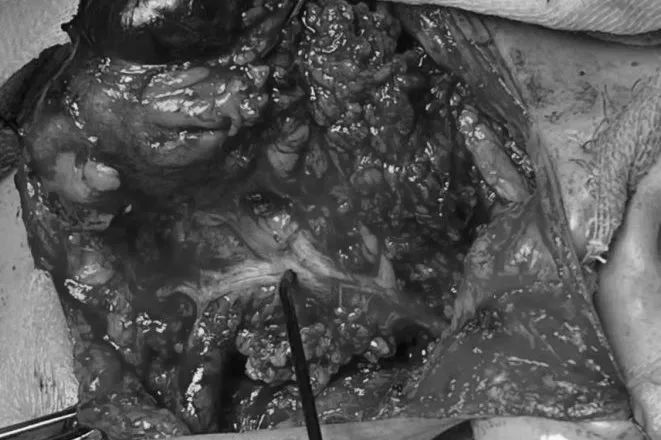

由于腮腺手术与面神经的关系十分密切,腮腺切除术犹如在面神经上「走钢丝」。在游离面神经时,如果肉眼无法区分面神经与周围组织,这时「术中神探」可以大显身手。通过将刺激器放置在疑似面神经的组织上(图 1),生理给予一定量的电流刺激,如果出现 CMAP 波(复合肌肉动作电位)(图 2),便可以确认该组织是面神经。这样既可以避免医源性损伤,还能保护面神经,最后,耳鼻喉科手术团队在神经电生理科术中监测团队的协作下成功安全切除了陈大爷的腮腺肿物。